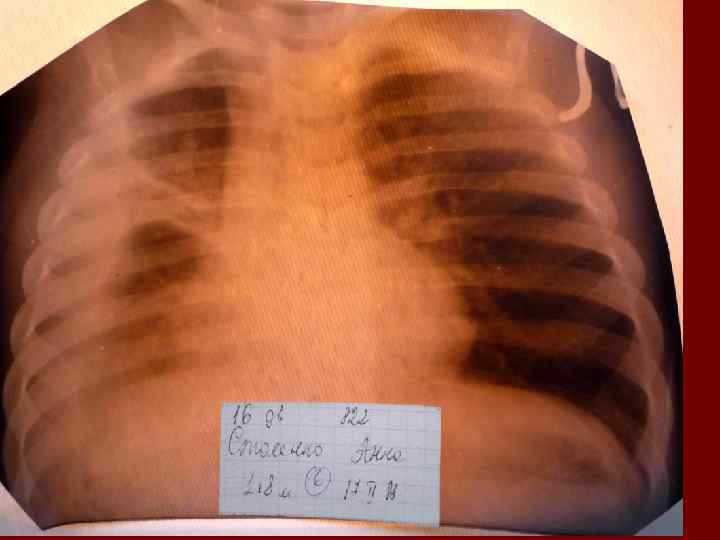

Пневмония Воспалительный процесс в респираторных отделах легкого с наличием внутриальвеолярной экссудации. n Это острое инфекционное заболевание легочной паренхимы, диагностируемое по синдрому дыхательных расстройств и/или физикальным данным при наличии очаговых или инфильтративных изменений на рентгенограмме. n Пневмония – это, прежде всего, клинический диагноз, который ставит врач у постели больного, и только затем подтверждает рентгенологически. n

Пневмония - это неспецифическое воспаление легочной ткани, в основе которого лежат инфекционный токсикоз, дыхательная недостаточность, водно – электролитные и прочие метаболические нарушение с патологическими изменениями во всех органах и системах детского организма. Заболевание диагностируется на основании синдрома дыхательных расстройств и/или физикальных данных и верифицируется рентгенологически выявлением инфильтративных изменений в легких.

Критерии диагноза негоспитальной пневмонии: 1. Острое начало заболевания с температурой тела выше 38, 0’С; 2. кашель с выделением мокроты; 3. физикальные признаки: притупление или тупой перкуторный звук, ослабленное или жесткое дыхание, очаг звонких мелкопузырчатых хрипов и/или крепитации; 4. лейкоцитоз ( больше 10 * 109) и/или палочкоядерный сдвиг ( больше 10%). Диагноз пневмонии является установленным при наличии у больного рентгенологического подтверждения инфильтрации легочной ткани и не меньше 2 – х клинических признаков из выше приведенных.

Показания к назначению рентгенологического исследования: - лихорадка в течение 3 и более дней при наличии кашля; - одышка; - цианоз; - выраженные симптомы интоксикации; - типичные аускультативные или перкуторные изменения ( особенно асимметричной локализации).

Т. о. пневмония, как инфекционно – воспалительное заболевание паренхимы легких характеризуется: * общей реакцией организма на инфекцию ( признаки интоксикации – ухудшение общего состояния, аппетита; лихорадка и др. ) локальными изменениями в легких при физикальном обследовании ( очаговым укорочением перкуторного тона, ослаблением дыхания, локальными хрипами и др. ); * инфильтративными затемнениями на рентгенограммах, которые ранее отсутствовали ( при этом нет других известных причин возникновения затемнения при рентгенологическом исследовании легких) обусловленными заполнением альвеол экссудатом, содержащим преимущественно полинуклеарные нейтрофилы; *кашлем; * дыхательной недостаточностью – ДН ( одышка, участие вспомогательной мускулатуры в акте дыхания и др. ) * развитием внелегочных осложнений ( поражение сердечно – сосудистой системы, ЦНС, почек и т. д. ).